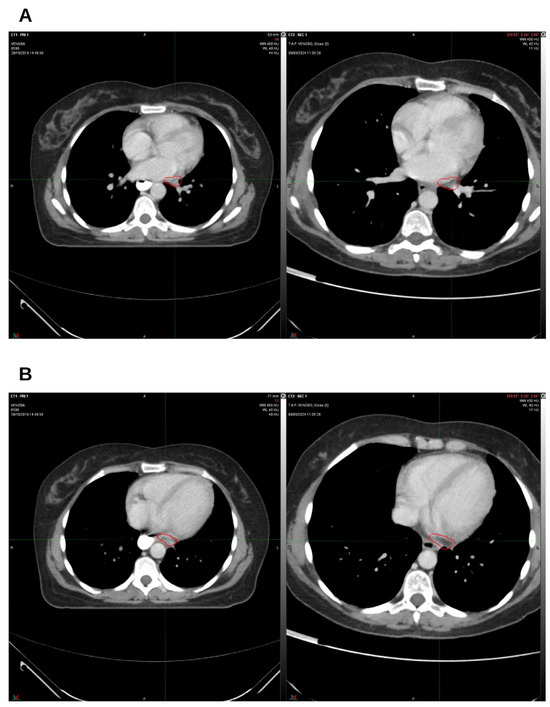

Integrative Use of Cannabidiol, Melatonin, and Oxygen–Ozone Therapy in Triple-Negative Breast Cancer with Lung and Mediastinal Metastases. A Case Report

Background and Clinical Significance: Breast cancer is the most frequent malignancy in women. Metastatic breast cancer is considered a treatable but incurable condition, with a median overall survival of only 2–3 years. Among its subtypes, triple-negative breast cancer (TNBC) accounts for a high proportion of breast cancer-related deaths. It is characterized by an aggressive clinical course, early recurrence, and a strong propensity for visceral and brain metastases. Case Presentation: We report the case of a Caucasian woman who developed systemic disease recurrence with lung and mediastinal lymph node metastases, occurring two years after her primary diagnosis and treatment for TNBC. The patient received three months of chemotherapy combined with an adjuvant integrative protocol consisting of melatonin, cannabidiol, and oxygen–ozone therapy. This combined approach led to the complete disappearance of the lung nodules. Subsequently, stereotactic radiotherapy was performed and, in association with the ongoing integrative treatment, resulted in a significant reduction in mediastinal adenopathy. Introduction of immunotherapy, supported continuously by the same adjuvant strategy, achieved a complete and durable remission. Strikingly, the patient remained disease-free five years after the diagnosis of lung and mediastinal metastases. Conclusions: This clinical case highlights the potential benefit of using melatonin, cannabidiol, and oxygen–ozone therapy as part of an integrative approach in patients with aggressive metastatic TNBC. While it is not possible to establish causality from a single case, the sustained remission observed suggests that such unconventional adjuvant strategies could play a supportive role in enhancing the efficacy of standard oncologic therapies. Full article

Figure 1